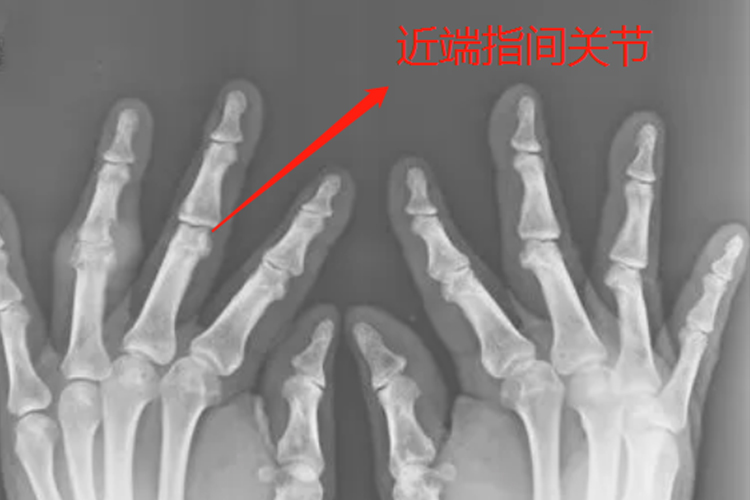

近端指间关节指的是近节指骨与中节指骨相关节处,由近节指骨与中节指骨以及周围软组织构成,是抓、握以及握拳的重要功能关节。

解剖学中将四肢更靠近肢根部的位置称为近端,更加靠近肩关节的指间关节被称为近端指间关节,由近节指骨与中节指骨相关节而成。关节囊附着于两骨关节面周缘,两侧有韧带与肌肉帮助固定。

近端指间关节是手部抓、握、握拳的重要功能关节,通常该关节的活动度比远端指间关节要大。大部分情况下仅允许屈曲,轻微的左右摆动和旋转。示指近端指间关节的屈曲范围为100°-115°,小指可达135°。